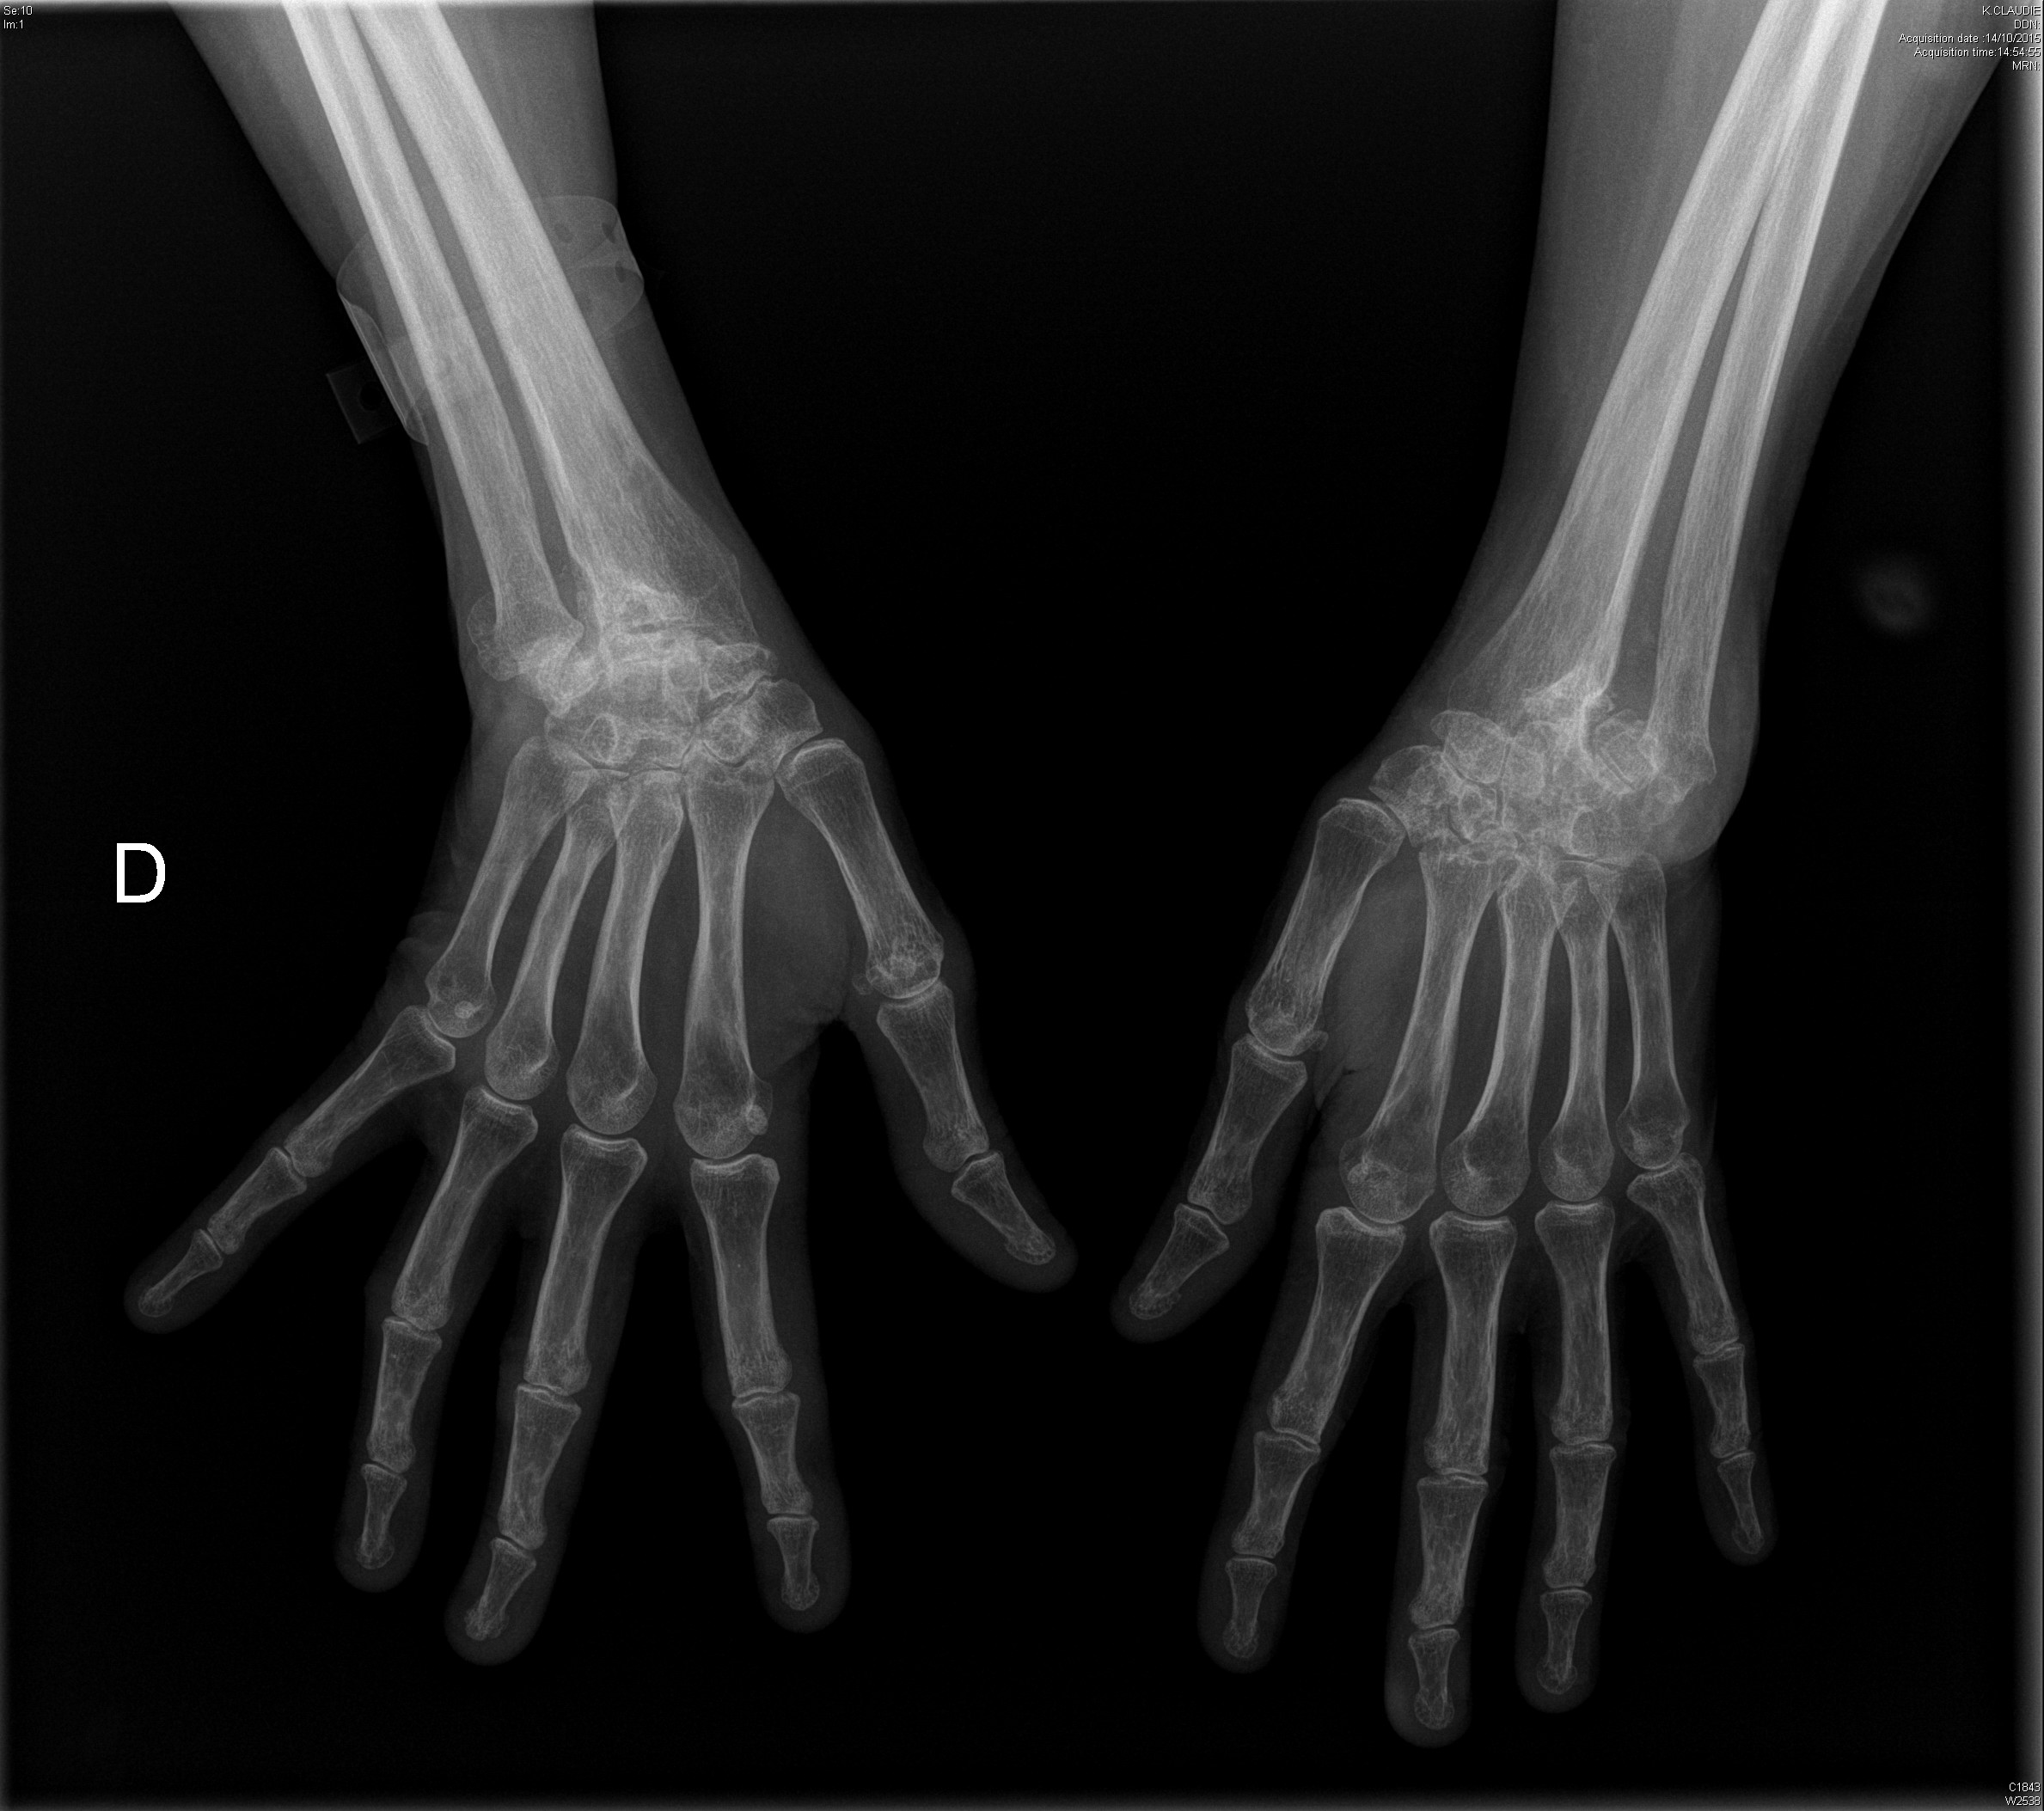

Carpite bilatérale évoluée dans le cadre d'une polyarthrite rhumatoïde

Polyarthrite rhumatoïde débutante, d'emblée érosive

polyarthrite rhumatoïde érosive avec signe de Freiberg radiographique au poignet